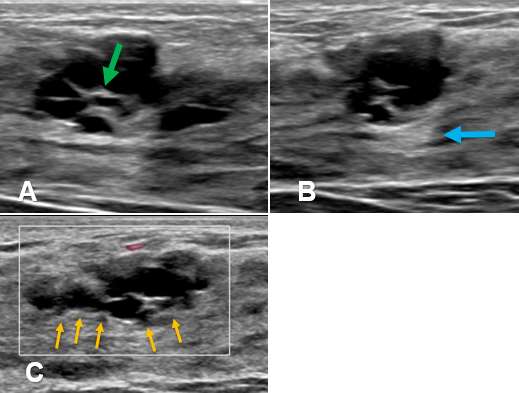

Case: Cysts figure 5

Figure 5A shows an oval lesion with fluid-debris level (blue arrow) that shifts with patient positioning (yellow arrow) in Figure 5B. There is an adjacent simple cyst (green arrow). Figure 5C demonstrates that the cyst does not exhibit vascularity within the hyperechoic debris components (orange arrow) confirming that there are no solid components.